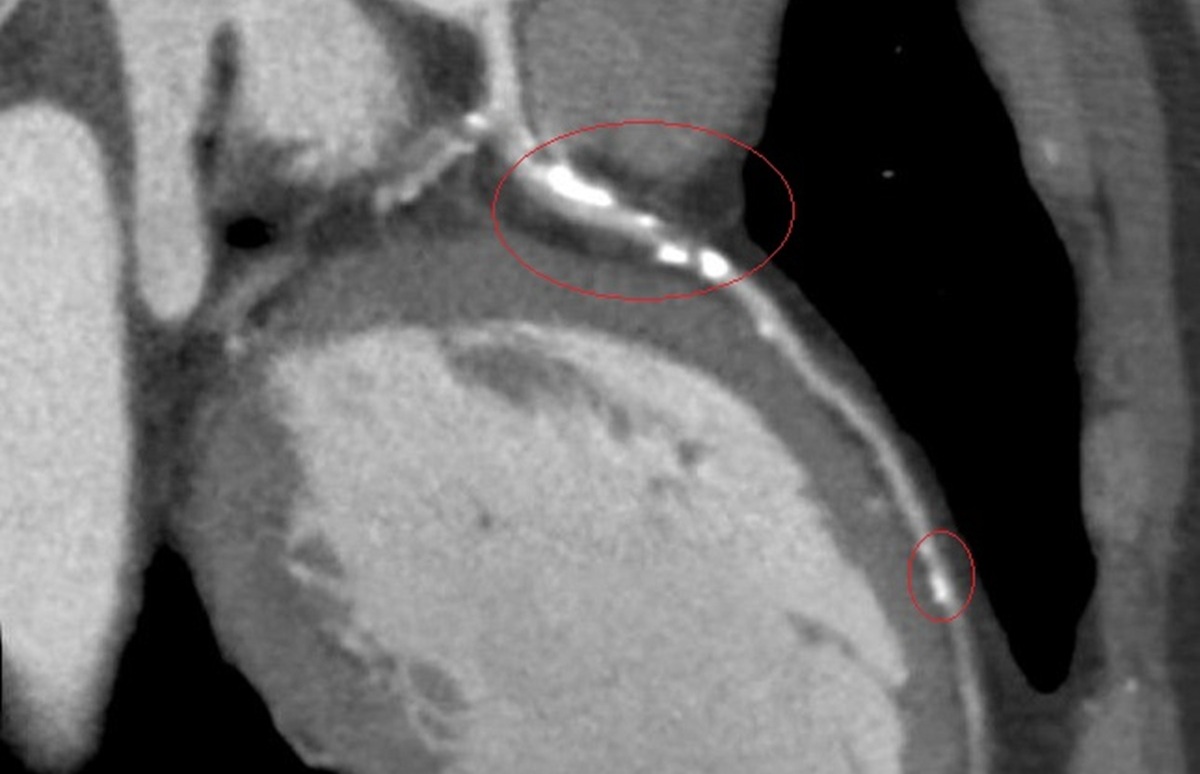

李學林說,醫療團隊透過心導管手術搭配 IVL技術,利用震波氣球貼近血管壁發出超聲壓力波,擊碎血管壁的堅硬鈣化斑塊,讓原本僵硬的血管恢復擴張性,為支架放置創造理想的環境,再植入3支支架,使支架能完整展開、貼合血管,降低支架血栓及再狹窄的風險。

李學林指出,臨床上約有三成冠狀動脈疾病患者伴隨中重度血管鈣化狹窄,鈣化讓血管變硬、難以擴張,造成治療挑戰。相較於傳統治療如切割球囊或鑽石旋磨術,IVL對血管壁更為溫和,能有效降低血管破裂與剝離風險,安全性更高,但目前該技術尚未納入健保給付。